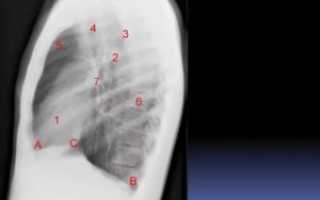

На рентгенограмме подписаны все анатомические структуры, чтобы читателям было легко разобраться. Предлагаем запомнить интенсивность легочных полей. Норма не предполагает наличия патологических затемнений (белого цвета) и просветлений (темного цвета), которых нет на изображении.

Если «набить глаз», научитесь четко отличать норму от патологии.

Рентген здоровых легких описывать следует по классическому стандарту. Вначале вносятся записи о патологических рентгеновских синдромах, затем легочные поля, корни, купола диафрагмы, реберно-диафрагмальные синусы, сердечная тень и мягкие ткани.

Классический алгоритм описания здоровых легких:

- В легочных полях без видимых очаговых и инфильтративных теней;

- Корни не расширены, структурны;

- Контуры диафрагмы и реберно-диафрагмальные синусы без особенностей;

- Сердечная тень обычной конфигурации;

- Мягкие ткани без особенностей.

Вышеприведенная рентгенограмма подпадает под данное описание.